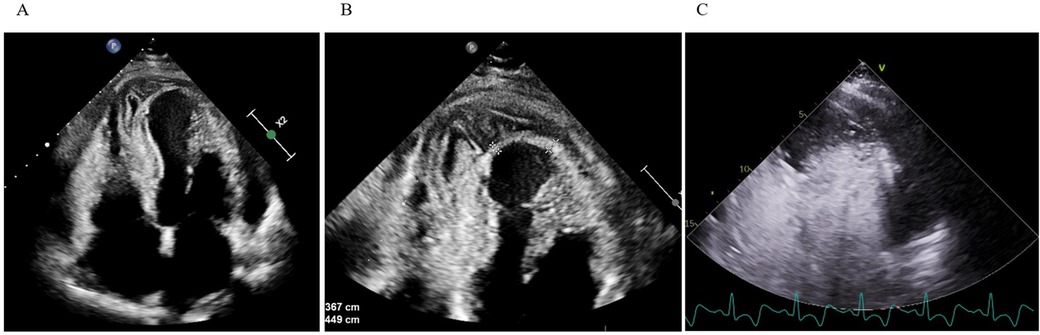

On day 31, the patient was transferred to the operating room, where first the median sternotomy and thorough adhesioloysis of the heart were performed. After sufficient exposure of the left ventricle, the LV aneurysm was opened and an endoventricular circular patch repair (i.e., Dor procedure) of the left ventricle performed using intraoperative tailored bovine pericardial patch (Abbot®, USA) shaped in an elliptical form measuring approximately 5 × 3 centimeters. Due to known ischemic aetiology of the disease no samples of the aneurysmatic tissue was sent for pathology, however, samples of the intramural hematoma were sent for microbiology to exclude the infective component of the disease (Figure 4). The chest was left open for delayed sternal closure and was subsequently closed on the next day once patient's complete hemodynamic stability and adequate haemostasis were established. No additional temporary mechanical circulatory support to achieve patient's hemodynamic stability was needed throughout the perioperative period.

Figure 4

The Dor procedure and outcome. (A) Median sternotomy reveals the heart exposed, showing extensive hematoma and inflammation involving the inferoapical myocardial region. (B,C) A synthetic patch for reconstruction of the LV geometry. (D) LV cavity exposed following resection of infarcted and necrotic myocardium. Sutures placed around the cavity for patch attachment. (E) Final positioning and fixation of the synthetic patch. (F) Postoperative TTE (apical four-chamber view) demonstrates successful resolution of the IDH and intracavitary thrombus, with only residual apical hypokinesis.

The patient tolerated the procedures well and was extubated on day two, post-operative course was insignificant. A TTE, performed 9 days after surgery revealed good LV systolic function with left-ventricular ejection fraction (LVEF) of 54% and slightly reduced left-ventricular outflow tract (LVOT) velocity-time integral (VTI) of 13 cm (stroke volume 22 mL/m2) with hypokinesia of apical septal segment and akinesia of apical inferior segment (Figure 4). Antibiotic treatment was completed on day 8 after surgery with no clinical signs of infection and low inflammatory markers.

Rehabilitation and functional recovery

The patient was enrolled in a structured cardiac rehabilitation program 1.5 months after the procedure, focusing on light aerobic exercises such as walking and stationary cycling, with gradual increases in intensity. Follow-up TTE showed LVEF of 48% with persistent apical hypokinesis but no residual hematoma or pericardial effusion. During her first stress test 1.5 months after the procedure, she achieved a workload of 79 watts [4.6 metabolic equivalents (METs)] without symptoms or complications. Her functional capacity gradually improved, reaching 87 watts (5.0 METs) 2 months after the procedure confirming successful recovery. At discharge from rehabilitation, she was capable of daily activities, advised to continue moderate exercise, and maintain regular follow-ups to ensure continued progress.